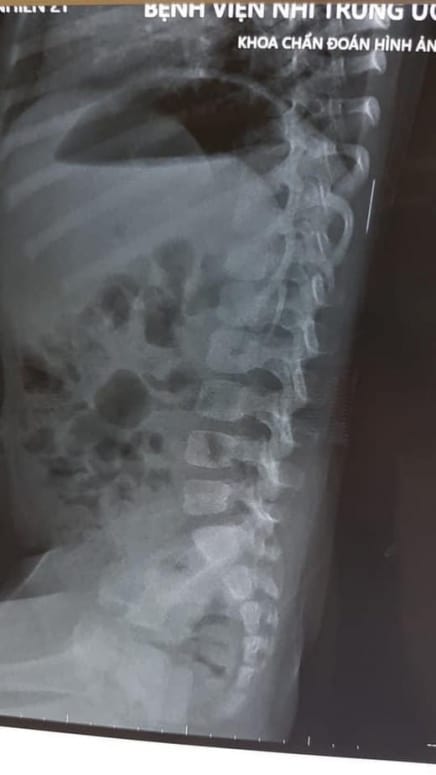

Tại Bệnh viện Nhi Trung ương, trong quá trình thăm khám, các bác sĩ đã tiến hành cho cháu chụp Xquang và phát hiện có dị vật trong phần mềm vùng cơ lưng trái, đốt sống 11.

Dị vật trong phần mềm vùng cơ lưng trái, đốt sống 11